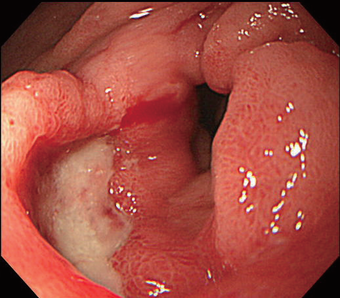

胃カメラや胃透視( バリウム)で診断します。胃透視では潰瘍の中にバリウムがたまったり、襞(ひだ)が集まったりする所見が見られます。内視鏡では円形~ 楕円形のくぼみがみられます(図1,2参照)。胃癌と区別がつきにくいため胃透視で診断された後でも内視鏡で一部の組織を採取して顕微鏡で検査が必要です。